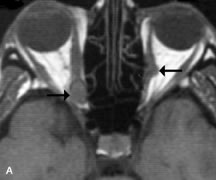

Fig. 20. A. T1-weighted MR scan demonstrates nodular enlargement of both medial rectus muscles (arrows). B. T1-weighted fat-suppressed contrast-enhanced scan confirms the presence of small metnstatic deposits within the muscles (open arrows).

Breast carcinoma metastatic to the orbit has been demonstrated to be hypointense to the surrounding orbital fat on T1-weighted studies and hyperintense on T2-weighted images and has an affinity to the extraocular muscles (Fig. 20).50,64 The MRI characteristics of prostate carcinoma metastatic to the orbit have been described as involving the greater and lesser wing of the sphenoid, orbital roof, and optic canal. Diffuse bone hypertrophy with isointense or slightly hyperintense tissue on T1-weighted images represents the osteoblastic carcinomatous bone infiltration. Contrast enhancement is variable on T1-weighted and fat-suppressed images.65